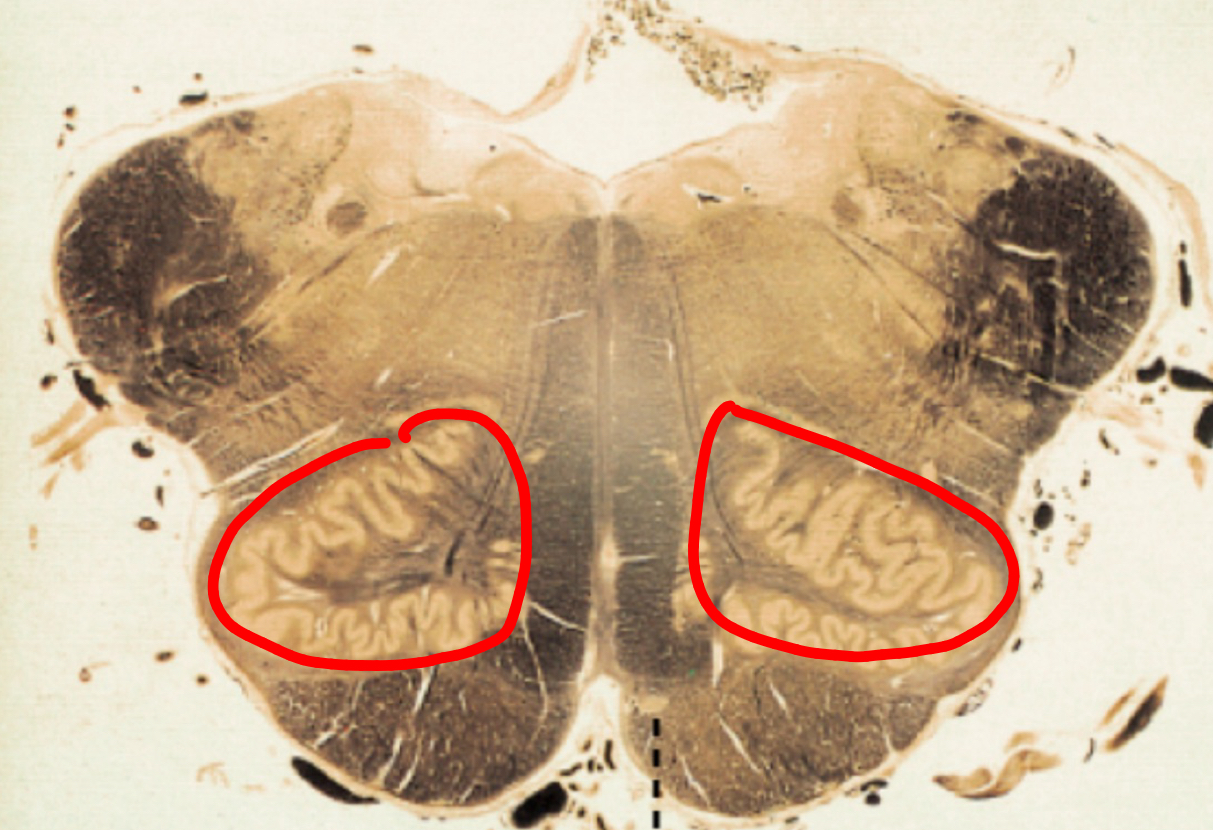

hippocampus with fimbria